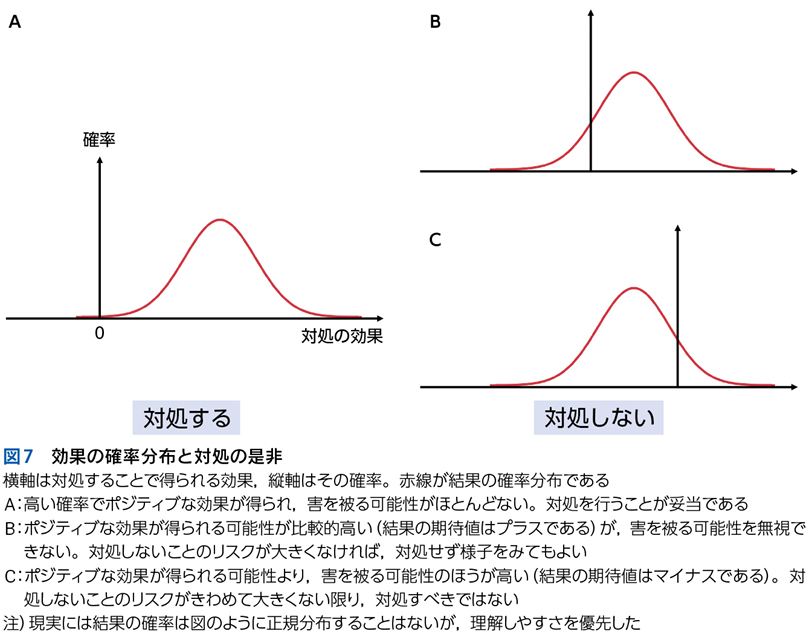

3 プロブレム/問題のyield

▶ フレームの広さを決めるのは,定義された問題の“yield”である。yieldとは「産み出す」というような意味で,定義された問題がどれほど診断に資するかによって,問題のyieldが高い(high yield),低い(low yield)という使い方をする。high yieldな問題によるフレームは狭く,可能な診断の数を大きく絞り,診断をぐっと近づける。言い換えれば,ある診断(の一群)に対して特異度が高い。一方で,low yieldな問題によるフレームは広く,鑑別診断を意味のある数に絞ることに役立たない(図3)。

▶ 症例によっては,ここまで述べたような条件を満たす問題を複数定義できることがある。この場合は,それぞれの問題が描くフレームが重なり合うところに診断があると考えるとよい(図3)。

▶ これらの問題はそれぞれが比較的high yieldであり,よいフレームとなりうる。3つのフレーム内でそれぞれ網羅的に鑑別を挙げ(その方法はステップ②で後述),重なるところに着目するとサルコイドーシスが診断の第一仮説に浮上する。ちなみにこのケースでは患者は発熱と失神も呈しているが,発熱はlow yieldであり鑑別を減らすのに役立たず(急性多関節炎,結節性紅斑,肺門部リンパ節腫脹を呈する疾患はほぼすべて発熱を呈してもおかしくない),失神はこのケースでは最終的に(心サルコイドーシスに起因するものではなく)発熱下での神経調節性失神という評価となり,サルコイドーシスの診断においてはノイズだった(二元論で説明される症状だった)ことがわかる(図7)。